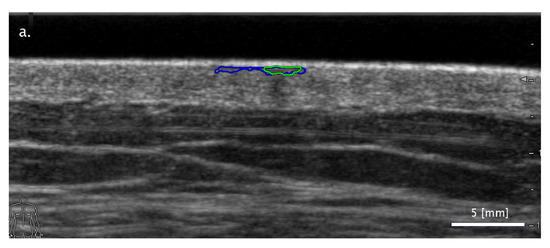

3.2. Comparison of FA and SA Classification Performance with Representative Images

3.2.1. Cases When FA Fails While SA Methods Perform Correctly

3.2.2. Cases When the Two SA Methods Return Different Classifications

3.2.3. Cases When the SA Methods Both Fail While the FA Method Performs Correctly

3.3. Sensitivity of Classification to Changes in Lesion Segmentation